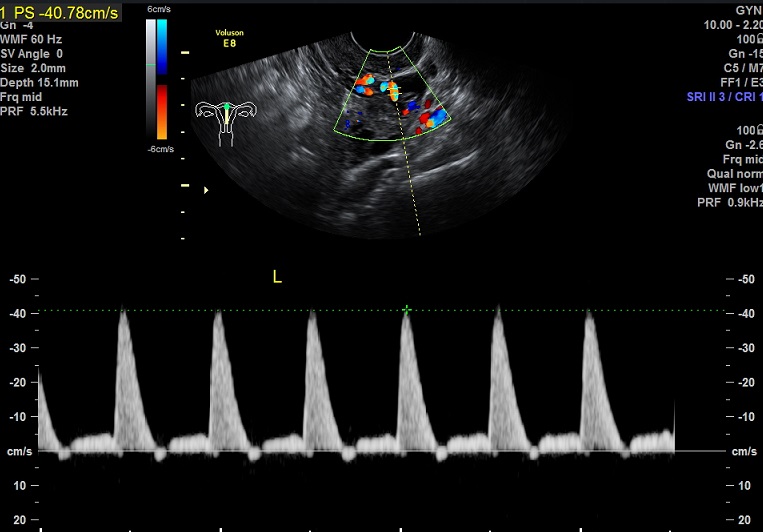

子宫动脉:

L:PSV:40.8cm/s ,舒张早期血流反向

R: PSV:55.9cm/s ,舒张早期血流反向